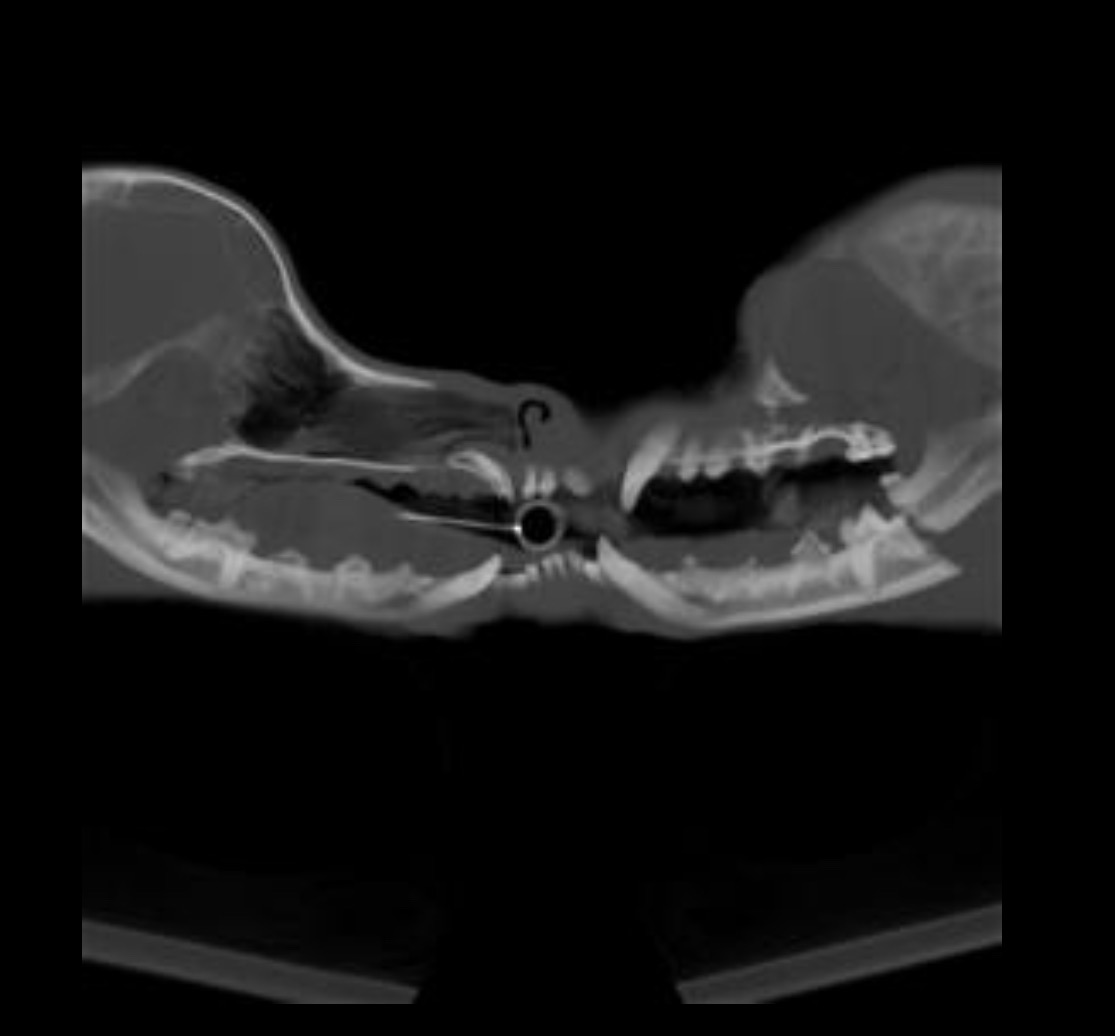

While doing laundry with Fred (who was on a leash and wearing a harness), an unleashed pitbull ran in and viciously attacked him, biting him directly on the face. The result? Fred’s jaw was fractured in the attack, and he was left bleeding and in excruciating pain. I had to pull Fred from the dog’s mouth myself, while the other dog's owner stood by and did nothing to help.

Fred was rushed to MASH Animal Hospital , where he underwent emergency treatment to stabilize his condition. He required major jaw surgery, including the placement of a metal plate to try to repair the fracture.

But now, the situation has taken a turn: The metal plate failed and Fred needs another $3,500 surgery to remove the plate and prevent further complications.